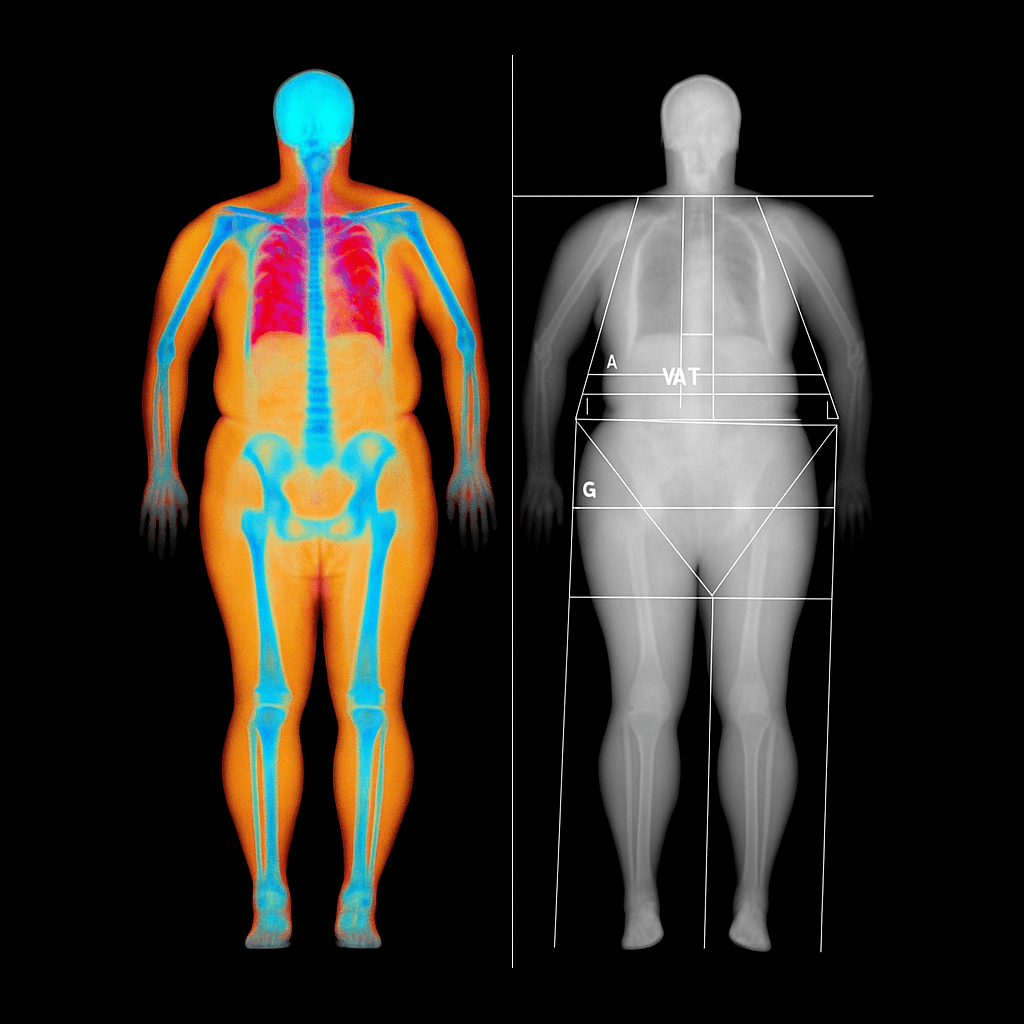

Vid en DEXA-mätning ligger du bekvämt på en brits medan en lågdosröntgen passerar över kroppen och mäter hur mycket strålning som absorberas av skelettet. Genom att använda två olika energinivåer kan apparaten skilja mellan ben, muskler och fettvävnad – vilket ger ett mycket exakt mått på bentätheten.

Undersökningen är helt smärtfri och tar cirka 10–25 minuter. Stråldosen är mycket låg, ofta lägre än vid en vanlig röntgenbild. Mätningen görs vanligtvis över höft och ländrygg, men kan vid behov även utföras på underarm eller som helkroppsskanning.